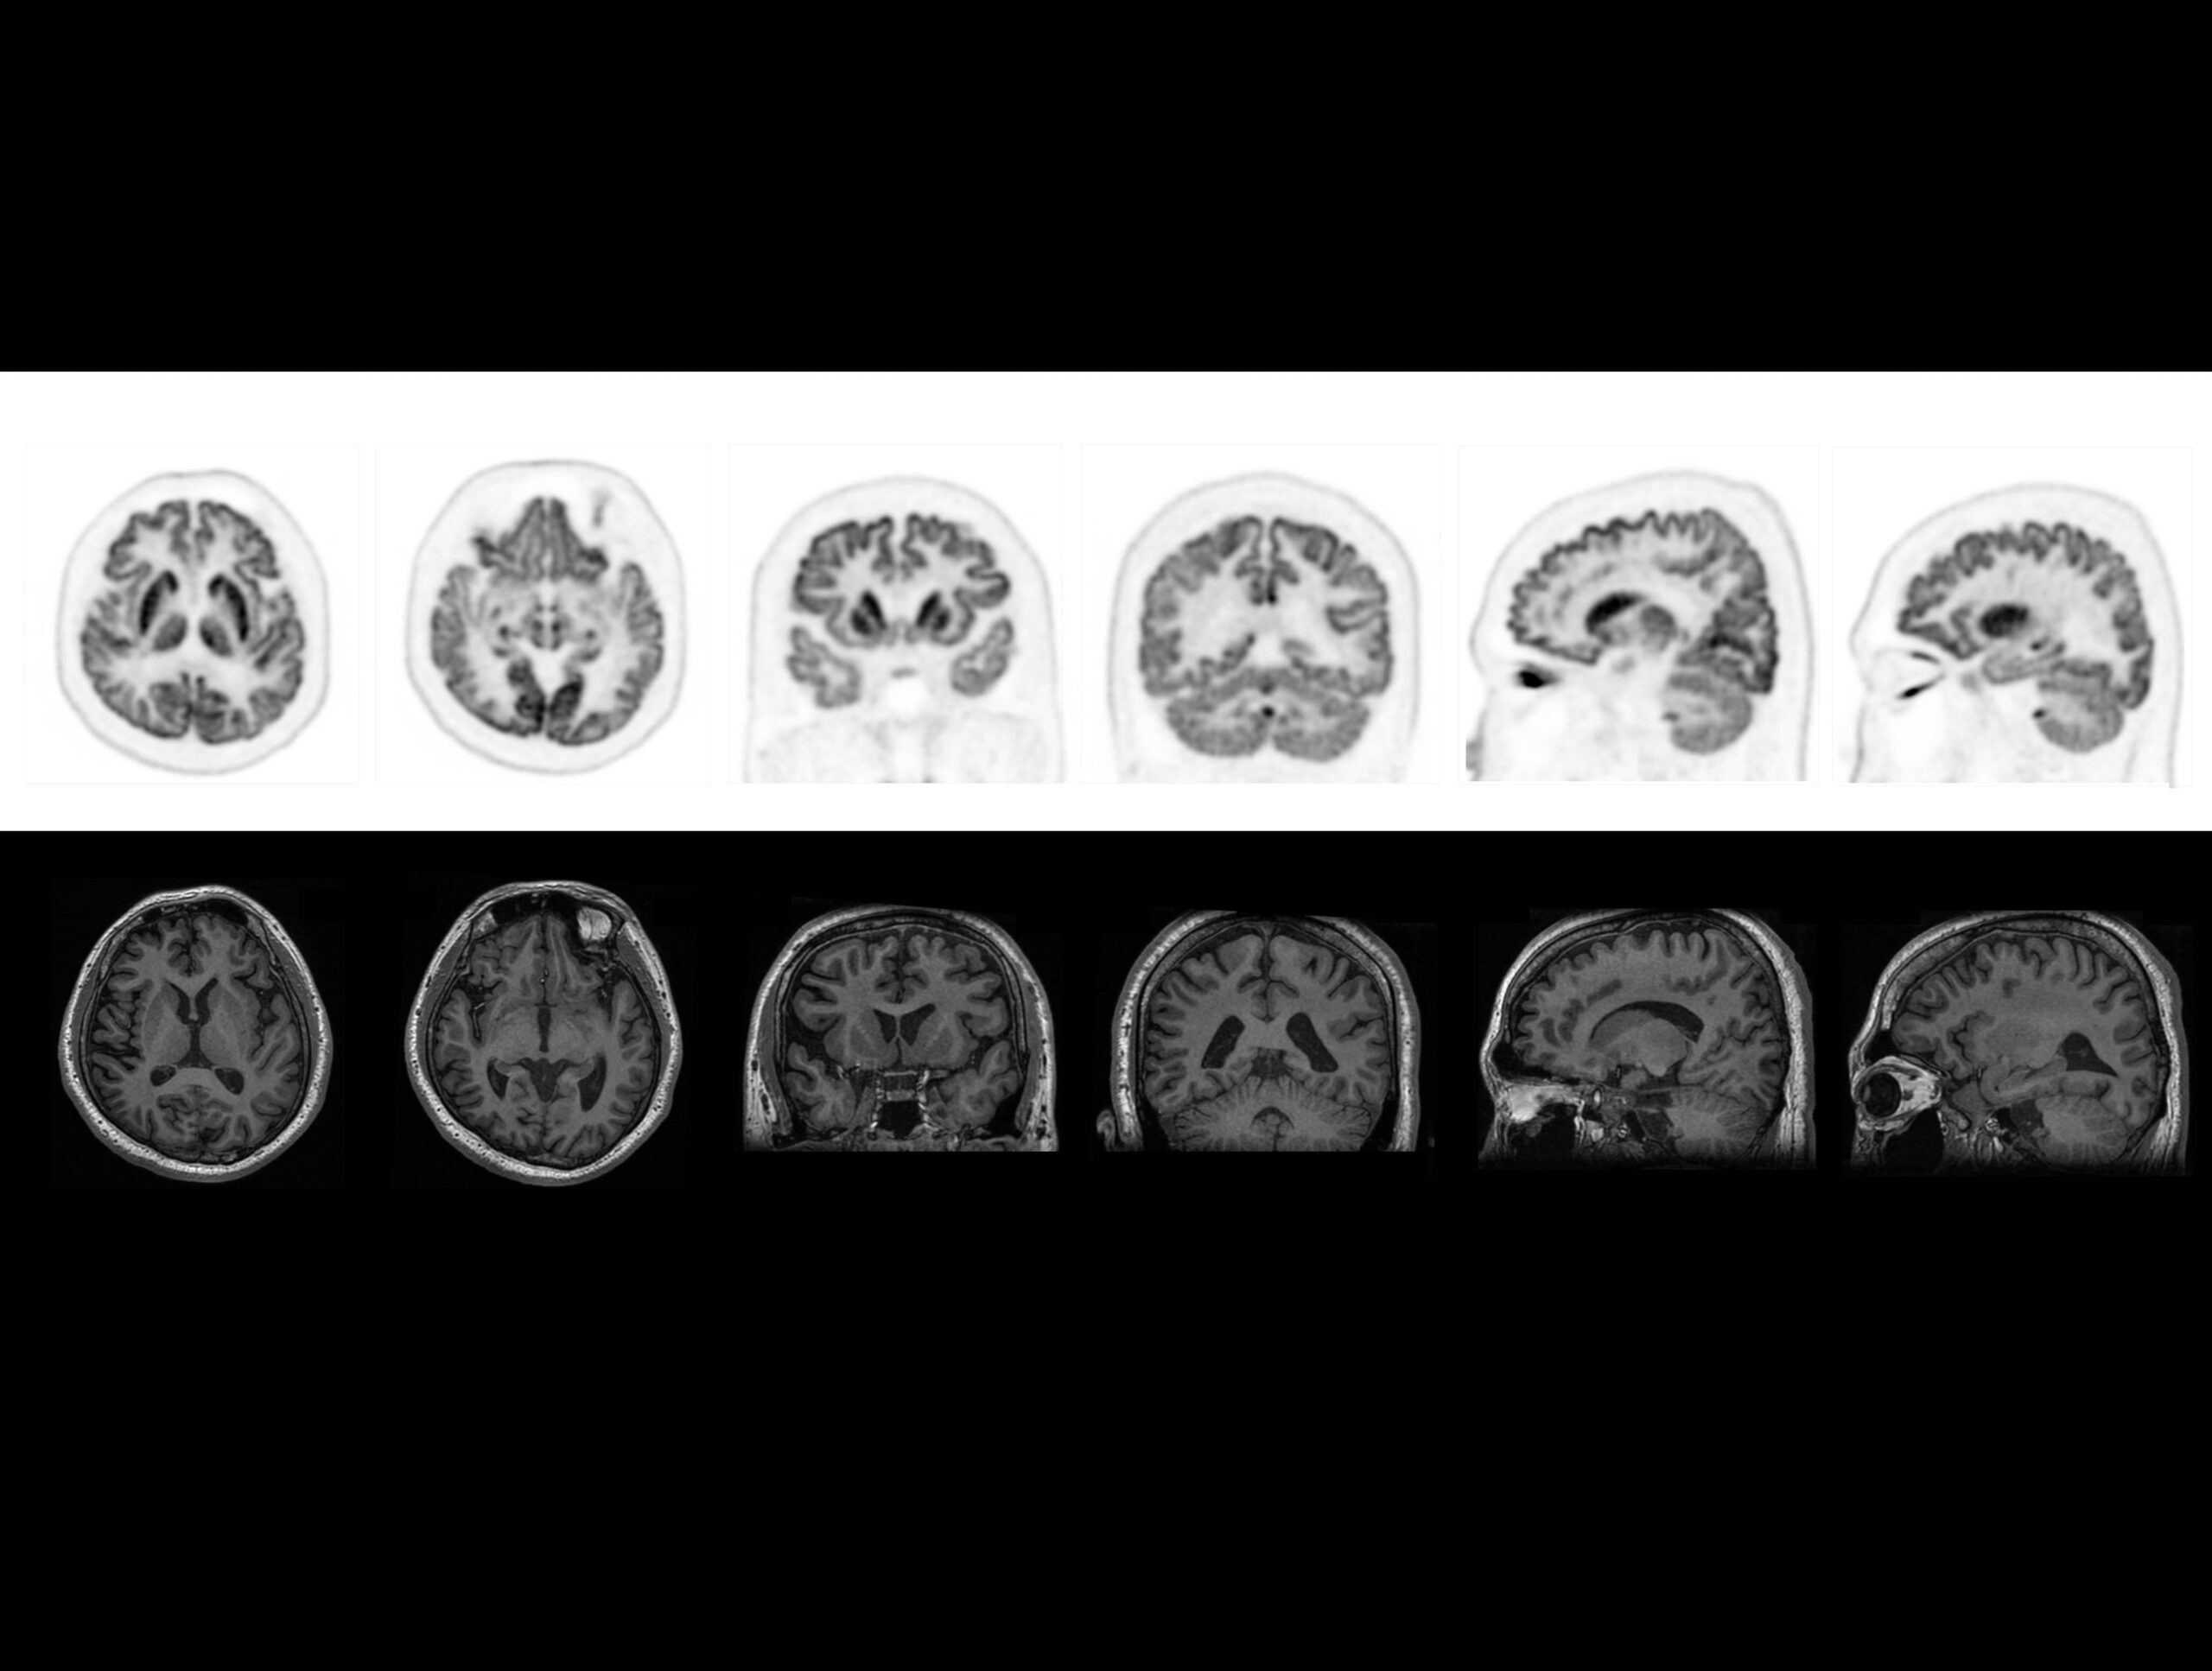

Performanța TOF îmbunătățește imagistica cerebrală PET high-resolution, cu informații anatomice și funcționale combinate

Tehnologia TOF oferă imagini high-definition ale substanței cenușii și albe la pacienții cu epilepsie, alături de RMN